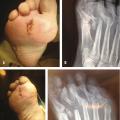

Les ostéo-arthrites métatarso-phalangiennes nécessitent la plupart du temps une résection de la tête métatarsienne (fig. 2 ) car celle-ci est le plus souvent de qualité médiocre avec un cartilage qui se décolle de l’os sous-chondral et l’os lui-même a un aspect de sucre mouillé. La résection sur la base de la phalange est souvent très limitée car l’atteinte osseuse est plus modérée. Si l’os est de bonne qualité, on peut se contenter d’une simple synovectomie associée à une ablation du cartilage avec régularisation de la tête métatarsienne, ce qui permet encore plus de limiter les risques de transfert d’appui sur les têtes voisines.